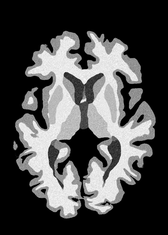

4.2 Registration to a 100 micron ex-vivo brain MRI volume

To showcase the efficacy of our method on real large scale images, we register a 250 in-vivo MRI image (Lüsebrink et al., 2017) to a 100 ex-vivo FLASH human brain volume (Edlow et al., 2019). This represents an inverse problem with more than 11.2B optimizable parameters (compared to 20M for clinical datasets), or 44.8GB of GPU memory. The entire problem does not fit on most GPUs, necessitating distributed multimodal registration. We optimize a composite transform - affine followed by a diffeomorphic mapping; details can be found in Section E.1. Multimodal deformable registration took 58 seconds on 8 NVIDIA A6000 GPUs, which is unprecedented at this resolution. Fig. 6 shows qualitative results, highlighting the ability to register highly detailed structures such as cerebellar white matter; these structures are not visible at macroscopic scales. The resultant advantages of performing registration at this scale can allow researchers to characterize the neuroanatomy at microscopic resolutions and allow morphometric analysis of cortical layers and subcortical nuclei among other structures.